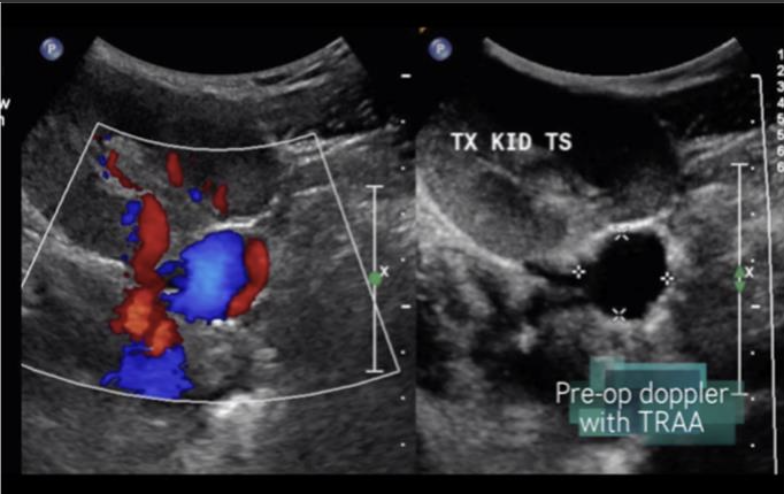

AVF (Arteriovenous Fistula) → abnormal connection between artery and vein in kidney

clinical hx: congenital, iatrogenic, spontaneous

s/sx: hematuria, flank pain, abdominal bruit

2D US: cystic space

color doppler: focal aliasing

DDX: aneurysm

Renal Artery Aneurysm → focal dilation of renal artery

clinical hx: congenital, inflammatory disease

s/sx: asymptomatic

2D US: cystic mass medial to renal hilum, connection to main artery

color doppler: helical flow

DDX: AVF

Renal Artery Stenosis → narrowing of renal artery

clinical hx: older adults, smoking, DM

s/sx: HTN that doesn’t respond to normal medical treatment

2D US: usually unilateral, compare affected kidney to unaffected, kidney is significantly smaller than contralateral kidney

color doppler: increased velocity in artery

DDX: atherosclerosis renal artery aneurysm